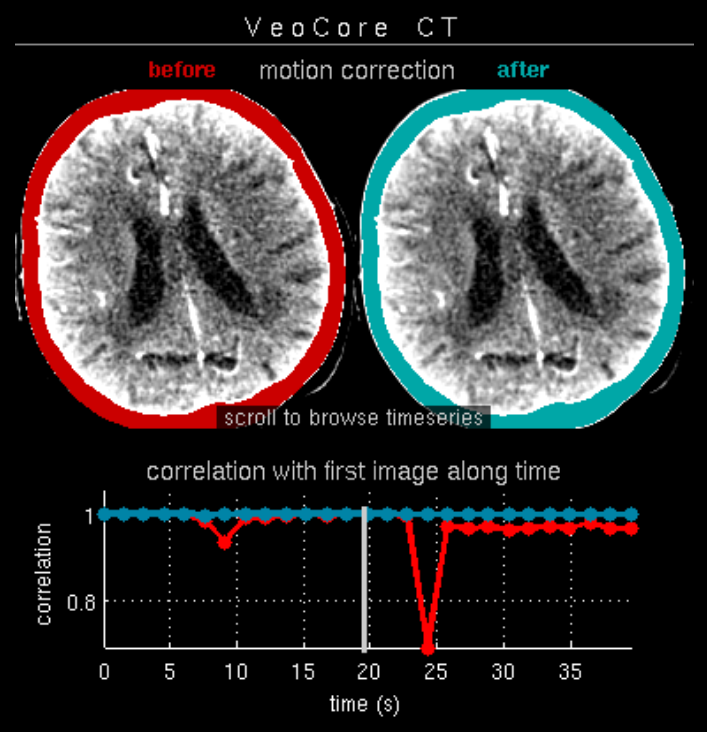

16.1. Overview

VEOcore is a fully automated image processing tool to calculate quantitative measures of affected brain tissue and healthy tissue. Therefore, this manual covers the instructions on how to interpret the results. It’s an extension the mRay Server application and the results can be viewed inside the mRay Client. Furthermore processed results can be automatically forwarded to the PACS.

16.2. Triggering the data processing

VEOcore does not have a user-interface. Data is processed fully automated on reception of DICOM series. All series should be sent in one rush, otherwise the data processing might be invoked multiple times, and result images might appear in the target PACS multiple times.

For MR and CT, the following DICOM images can be sent to the application. For details on series naming conventions as well as compatible and recommended measurement parameters such as slice thickness, repetition times etc. please refer to the Annex.

16.2.1. Computed Tomography (CT))

-

CT perfusion (VPCT)

Repeatedly acquired volumes of low-dose CTs acquired during injection of a contrast bolus. This series is often called VPCT (Volume-Perfusion-CT). -

Non-contrast native CT image (optional)

Native image before contrast injection with a reconstruction kernel optimised for brain tissue. Sending this image is optional, but recommended. If sent together with the VPCT, it is used as background for the overlay with the segmented core and mismatch volume.

16.2.2. Magnetic Resonance Imaging (MRI)

-

MR perfusion (DSC-Perfusion) (optional)

Repeatedly acquired volumes of echo-planar imaging acquired during injection of a contrast bolus. This measurement technique is often referred to as DSC-Perfusion (Dynamic-susceptibility-contrast perfusion). Sending a perfusion measurement is optional in MR. If not send, only the infarction core will be segmented based on the ADC (see below). -

MR ADC

Apparent-Diffusion-Coefficient (ADC), berechnet aus einer diffusions-gewichteten Sequenz (DWI-MR). Das senden des direkt am MR-Scanner berechneten ADC ist unbedingt notwendigan ADC, VEOcore berechent keinen ADC selbst aus den DWI-Daten. -

MR DWI (optional)